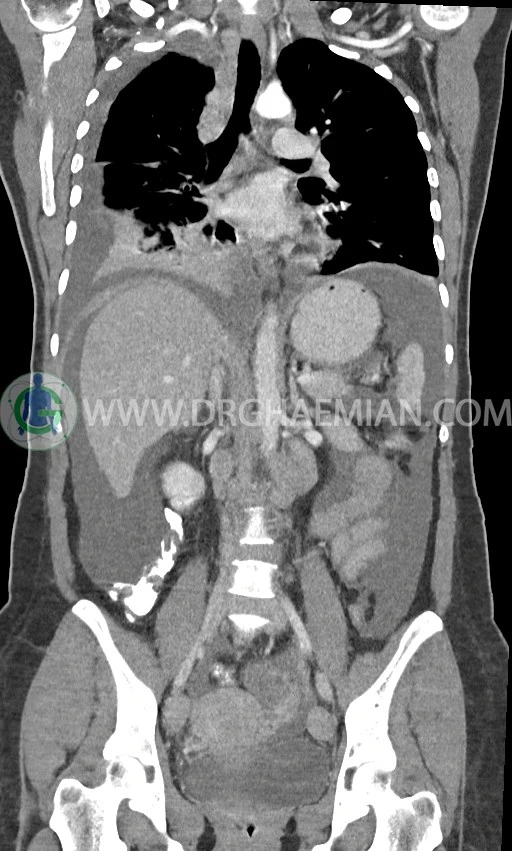

در سی تی اسکن اسپیرال ریه، مدیاستن و شکم و لگن با کنتراست خوراکی و وریدی (مولتی دیدکتور 16 با مقاطع ظریف و بازسازی های ساژیتال و کرونال) :

pleural effusion قابل توجه دوطرفه همراه با passive collapse سگمان های بازال (با شدت بیشتر در سمت راست)

اسیت قابل توجه در حفره شکم و لگن

انفیلتراسیون تومورال در قسمت های مختلف اومنتوم (omental cake)، به ویژه در قسمت تحتانی حفره شکم و لگن

توده سالید – سیستیک به ابعاد 40x60mm در تخمدان چپ و به ابعاد 20x40mm در تخمدان راست و

لنفادنوپاتی فراوان در اطراف آئورت و IVC با حداکثر SAD= 25mm در دیواره دو طرف حفره لگن با حداکثر SAD= 20mm

مشهود است.